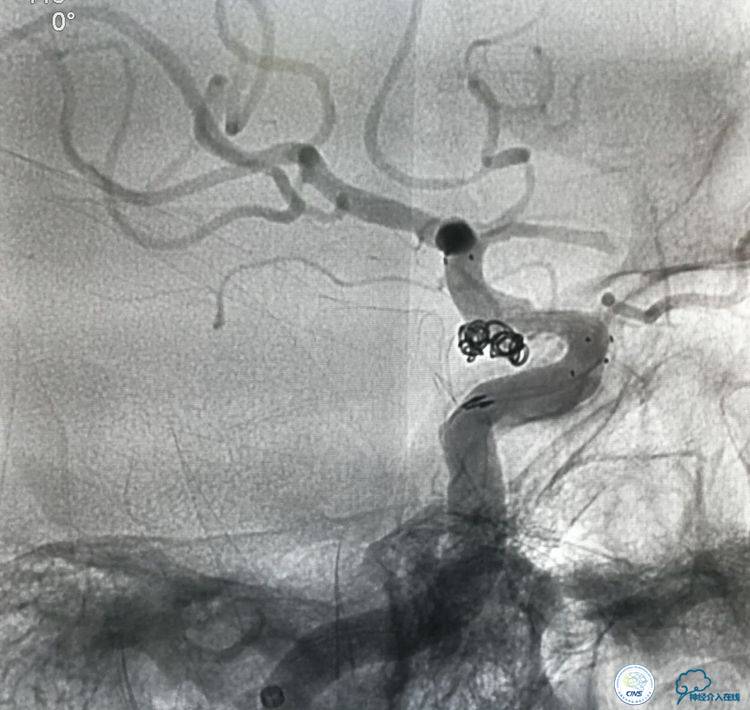

▼将微导管超选择到动脉瘤腔内。

▼2个微导管到位。

▼分别进行栓塞。

▼动脉瘤致密栓塞,血管狭窄改善,载瘤动脉通畅。